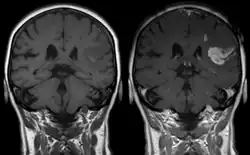

Effect of contrast agent on images: Defect of the blood–brain barrier after stroke shown in MRI. T1-weighted images, left image without, right image with contrast medium administration

Gadolinium(III) containing MRI contrast agents (often termed simply "gado" or "gad") are the most commonly used for enhancement of vessels in MR angiography or for brain tumor enhancement associated with the degradation of the blood–brain barrier (BBB).[3][4] Over 450 million doses have been administered worldwide from 1988 to 2017.[5] For large vessels such as the aorta and its branches, the dose can be as low as 0.1 mmol/kg of body mass. Higher concentrations are often used for finer vasculature.[6] At much higher concentration, there is more T2 shortening effect of gadolinium, causing gadolinium brightness to be less than surrounding body tissues.[7] However at such concentration, it will cause greater toxicity to bodily tissues.[8]

Gd3+ chelates are hydrophilic and do not readily cross the intact blood–brain barrier. Thus, they are useful in enhancing lesions and tumors where the blood–brain barrier is compromised and the Gd(III) leaks out.[9][lower-alpha 1] In the rest of the body, the Gd3+ initially remains in the circulation but then distributes into the interstitial space or is eliminated by the kidneys.